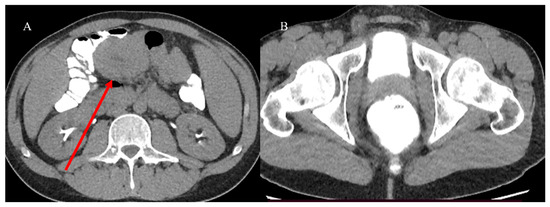

- Chao, T.C.; Chao, H.H.; Jan, Y.Y.; Chen, M.F. Perforation through small bowel malignant tumors. J. Gastrointest. Surg. 2005, 9, 430–435. [Google Scholar] [CrossRef] [PubMed]

- Mooghal, M.; Ahmad, A.; Safi, A.; Khan, W.; Ahmad, N. Impending perforation near ileocecal junction due to phytobezoar impaction and intraluminal polyp: A case report. J. Med. Case Rep. 2022, 16, 124. [Google Scholar] [CrossRef] [PubMed]

- Carney, B.W.; Khatri, G.; Shenoy-Bhangle, A.S. The role of imaging in gastrointestinal bleed. Cardiovasc. Diagn. Ther. 2019, 9 (Suppl. S1), S88. [Google Scholar] [CrossRef]

- Pouli, S.; Kozana, A.; Papakitsou, I.; Daskalogiannaki, M.; Raissaki, M. Gastrointestinal perforation: Clinical and MDCT clues for identification of aetiology. Insights Imaging 2020, 11, 31. [Google Scholar] [CrossRef]